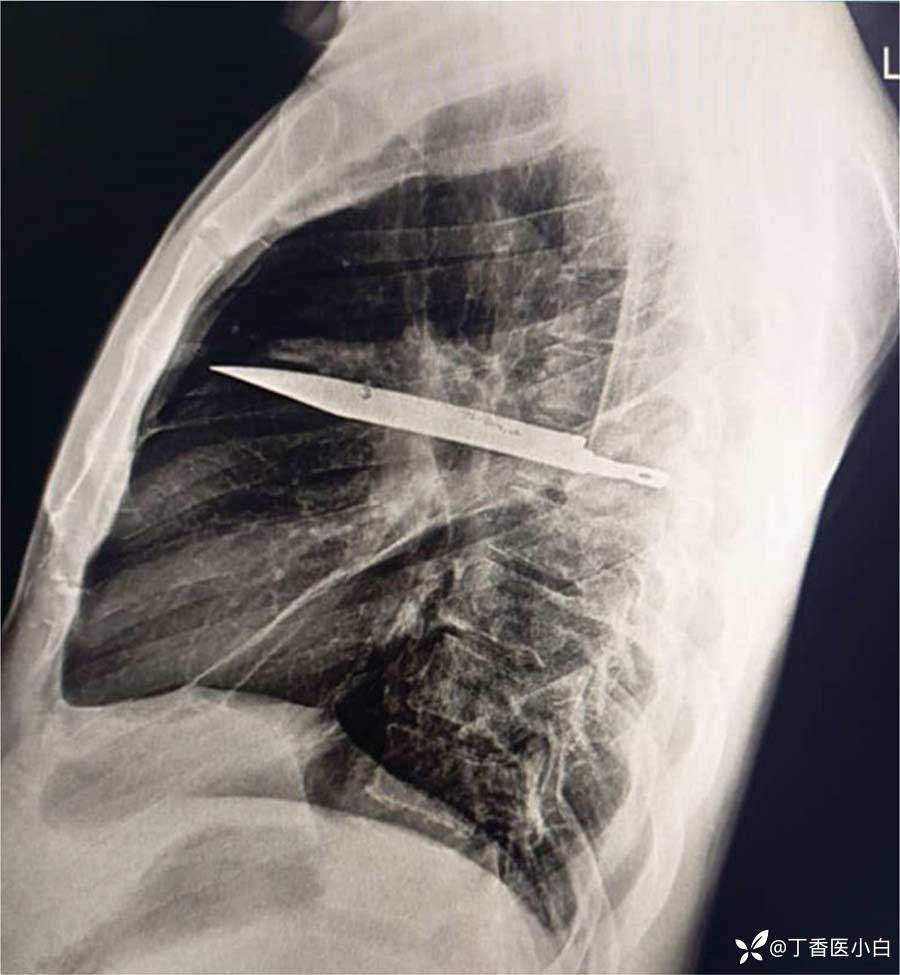

X光片显示,这名男子的胸部内嵌着一把巨大的金属刀片,位于三四肋骨间。CT扫描显示,他的肩胛骨和几根肋骨有愈合的骨折。刀刃周围被脓液和坏死组织包裹。其余肺实质未见异常。

刀片卡在胸部中部